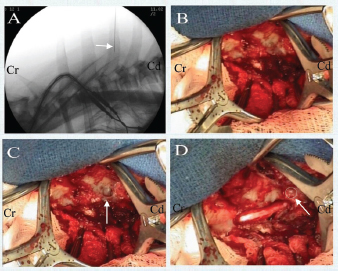

In five of the six cases, the surgical site was identified by fluoroscopic guidance using a C-arm (SIREMOBIL Compact L, Siemens Healthcare) and spinal needle (Fig. 4A); once the spinal needle was aligned with the spinous process of interest, the stylet was removed and the needle cut at the level of the skin with a pin cutter and a final sterile prep performed. The placement of the spinal needle to identify the surgical site allowed the most minimal approach to be made, which further spared extensive muscle dissection. In one case, the surgical site was identified by palpation of the T1 spinous process.

After standard draping, the skin was covered with an additional antibiotic drape. Approach and exposure of the vertebrae was similar to a standard thoracolumbar hemilaminectomy described by Sharp and Wheeler (2005), performed by removing the muscle and its insertions/tendons from the vertebrae of interest as well as one to two vertebra cranial and caudal, followed by bony removal of the facet joint between vertebrae and ultimately removing the side of the vertebra along the area of spinal cord compression (typically creating an elongated rectangular defect in the cranial and caudal aspect of the vertebral bodies). By following the previously placed spinal needle, we minimized dissection of the surrounding muscle and its insertions solely to the vertebrae of interest. The subcutaneous tissues were retracted to reveal the thoracic fascia, which was incised in a paramedian fashion on the side of the lesion to avoid damage to the supraspinous ligament. Exposure of the vertebrae of interest was achieved by elevation of the transversospinalis and longissimus muscles from the spinous process, vertebral arch, and transverse and mamillary process, exposing the intervertebral foramen (Fig. 4B). Muscle retraction was maintained with Gelpi (Integra) retractors, and bleeding was controlled with bipolar electrocautery.

A 3–5 mm pilot hole was created, preferentially in the lamina of the caudal vertebra of interest, using a pneumatic drill (Hall Surgairtome Two, West Coast Medical Equipment) with a round burr in order to identify the orientation of the spinal cord prior to continuing the hemilaminectomy (Fig. 4C). The hemilaminectomy could then be shaped on a case-by-case basis to provide ideal visualization of spinal cord compression, incorporating the pilot hole depending on its initial accuracy (Fig. 4D). This technique is further illustrated in Figures 5 and 6. There is a minimal associated risk, and the pilot hole allows the surgeon to tailor the hemilaminectomy window appropriately to maximize the removal of compressive material while minimizing trauma to the venous sinus, spinal cord, and ventral nerve root. This also guides the surgeon in removing a portion of the caudal aspect of the transverse process, which facilitates additional visualization and removal of compressive material.

Fig. 4. View from the left side of midline with the head to the left of the picture. Cr indicates the cranial portion of the patient and the caudal portion of the patient is indicated by Cd. (A) Identification of surgical site using a spinal needle (arrow) and fluoroscopic guidance at T3 in Dog 1. (B) Dissection to expose T3 and T4 of Dog 1. (C) Pilot hole (arrow) created in caudal aspect of T4 of Dog 1. (D) Hemilaminectomy at T3–T4 of Dog 1. The pilot hole can be seen caudodorsal to the hemilaminectomy (outlined with a circle), illustrating the use of the pilot hole as a guide for the ultimate ideal placement of the hemilaminectomy.